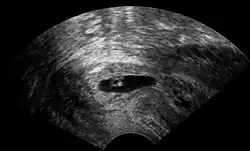

Vaginal ultrasonography of a cervical pregnancy at a gestational age of five weeks. See image below for details of the visible structures.[1] | |

The diagnosis is made in asymptomatic pregnant women either by inspection seeing a bluish discolored cervix or, more commonly, by obstetric ultrasonography. A typical non-specific symptom is vaginal bleeding during pregnancy. Ultrasound will show the location of the gestational sac in the cervix, while the uterine cavity is "empty". Cervical pregnancy can be confused with a miscarriage when pregnancy tissue is passing through the cervix.